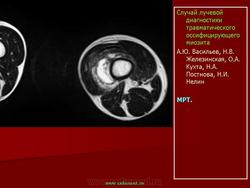

Описывается клинический случай редкого заболевания — оссифицирующего миозита — у девочки 11 лет. Представлены данные литературы, касающиеся этого заболевания.